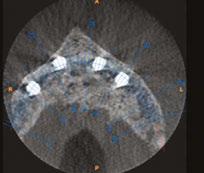

on the crest of the ridge in the region of teeth Nos. 15-25. While creating the incision, bleeding was noticed in the region of tooth No. 15 which intensified during the flap reflection (Figure 2). Bleeding was pulsatile, indicating an arterial bleed. Initially attempts to control bleeding included a pressure pack and ice pack, and the bleeder was isolated, and the vessel ligated (Figure 3). The bleeding could be controlled, and the procedure was completed by placing four Bioner implants (Bioner, Spain), size 4/10 mm. Sutures were placed, and patient was kept on basic medication for pain and infection control. Immediately after the surgery, the patient was advised to get a CBCT. As shown in Figure 4, a coronal view and Figure 4B (yellow arrows), the position of the artery can be seen.

Figure 1: Pre-op panoramic radiograph Figure 2 (left): Alveolar antral artery (AAA). Figure 3 (center): The artery has been ligated with suture. Figures 4A and 4B (right): CBCT post-implant placement and position of the artery coronally (top). 4B. Showing the position of alveolar antral artery (AAA) in relation to implant placement as indicated by the yellow arrows (bottom)